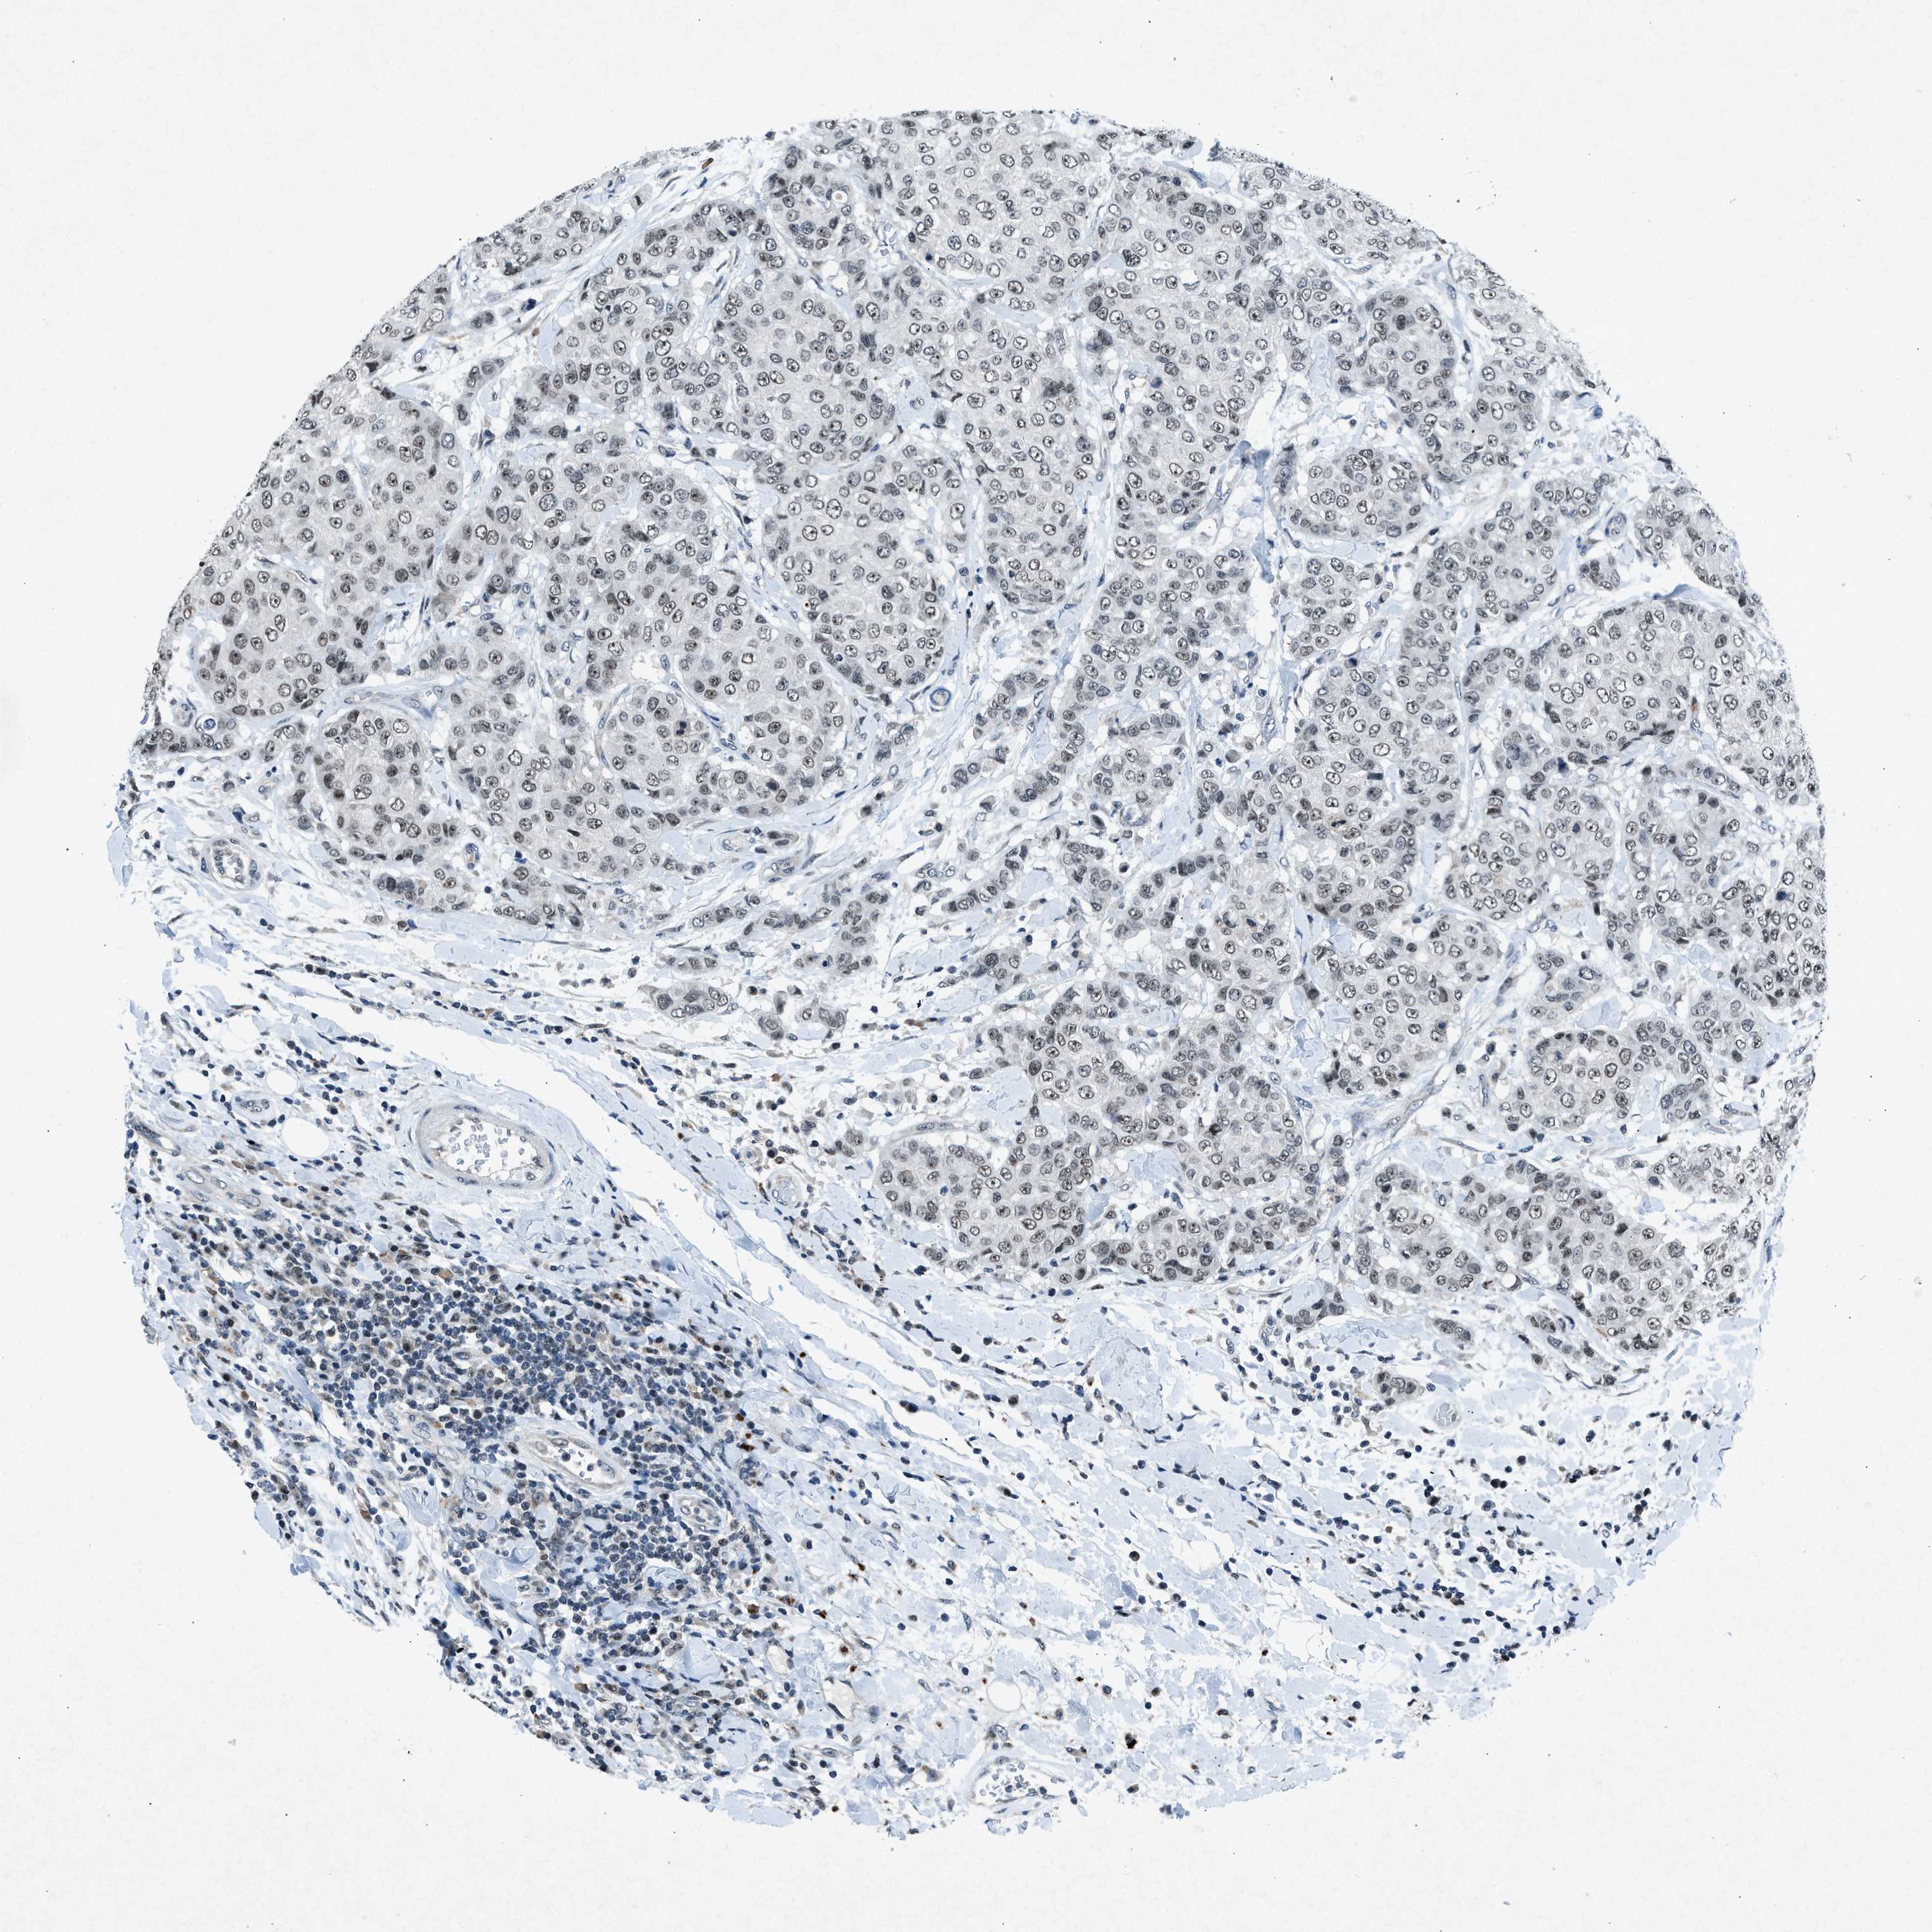

CANCER BREAST CANCER Show tissue menu

BRCA TCGA BRCA VALIDATION PROTEIN EXPRESSION

Breast cancer

Human cancer

Breast invasive carcinoma